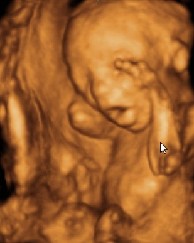

一個21周大的胎兒超聲波圖像(左)及根據(jù)超聲波圖像制成的21周大的胎兒模型(右)

據(jù)英國《每日郵報》6月26日報道,正在英國皇家藝術學院學習設計的博士生、來自巴西的豪爾赫·洛佩斯的這項研究成果將于26日在英國皇家藝術學院舉行的展覽會上進行展示。該研究成果是利用快速成型技術(rapid prototyping),將超聲波和核磁共振成像的數(shù)據(jù)進行轉換并制成與腹中胎兒一般大小的石膏模型。

一種更便于理解快速成型技術如何工作的好方法是:想象你在用一臺打印機打印,打印出的是石膏粉末而不是油墨,接著打印出一層又一層,逐漸就形成了一個3D模型。